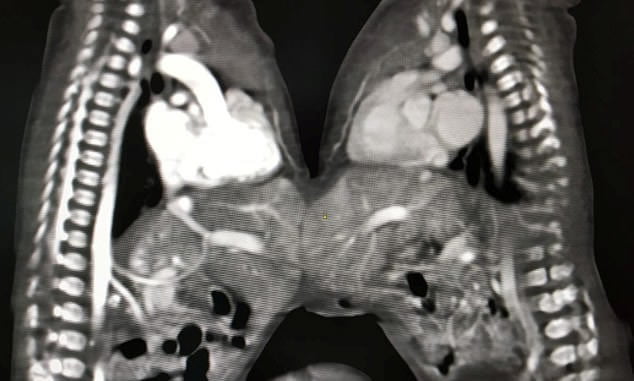

連體嬰兒非常罕見,但世界各地都曾出現過。印度就有一對連體雙胞胎女嬰,她們的胃部相連,出生3天體重只有3公斤。醫生認為通過手術將兩個嬰兒分離是最好的選擇。父母擔心手術有危險,但最後還是被醫生說服了。

▼5名外科醫生、10名醫生和15名護士共同努力了5個小時,手術終於成功了。這兩個女嬰很快就可以出院。因為孩子的父母無力承擔醫療費用,醫院決定免費為她們做手術。